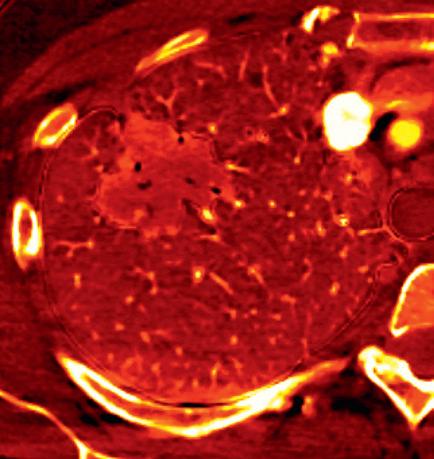

Most DECT datasets can be used to generate additional virtual monoenergetic images (typically between 40 and 60 keV [kilo electron volts]) that have high-contrast enhancement because they are close to the k-edge of the iodine. To minimize contrast streak artifacts and image noise in larger patients, higher keV images ( >70 keV) may be necessary. Iodine or pulmonary blood volume images represent material decomposition images (obtained from subtracting water from contrast-enhanced DECT images) that provide information on distribution of iodine in the lungs or remainder of the chest depending on the selected settings. The absolute iodine concentration expressed as milligrams per milliliter can be calculated from pulmonary blood volume images (Fig. 1.10). One can also generate water or virtual noncontrast images from contrast-enhanced

FIGURE 1.10 Estimation of iodine density in lung cancer. A standard computed tomography image (A) demonstrates an enhancing mass in the right upper lobe, particularly in the anterior aspect of the mass. The absolute iodine concentration expressed as milligrams per milliliter can be calculated from pulmonary blood volume (PBV) images (B)